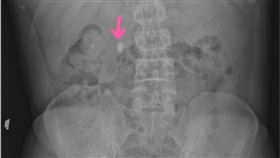

男狂喝1飲料!膀胱塞35顆石頭 恐怖成分曝

不少人喜歡喝碳酸飲料,但小心飲用過量可能危害健康。泌...

膀胱卡12顆巨石 醫切開赫見大魔王

人一生中會有10%的機率發生結石,尿路結石有多痛,過...